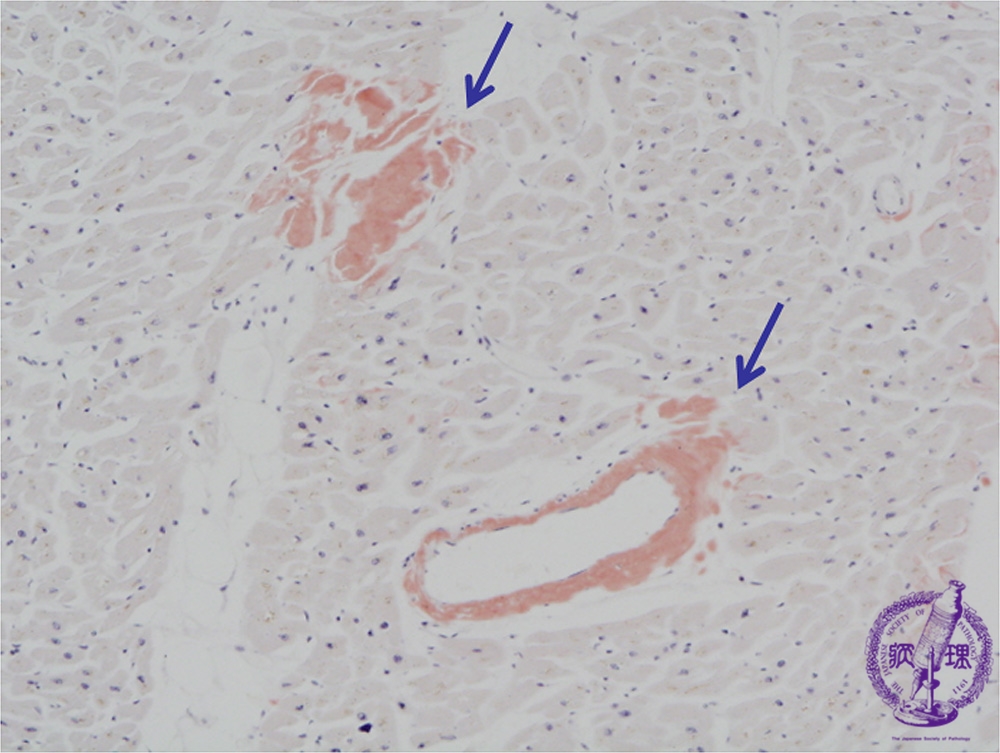

Microscopic image (Congo-red stain, low power view): There are small deposits of amorphous substance on HE staining composed of amyloid as demonstrated by Congo red stain (arrow). Amyloid deposition is confirmed by polarized light microscopy, which shows focal apple green birefringence.